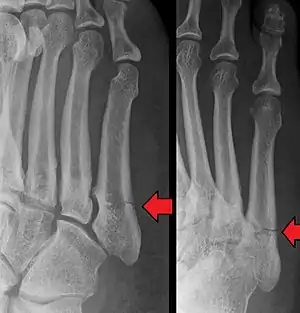

Other proximal fifth metatarsal fractures exist, although they are not as problematic as a Jones fracture. If the fracture enters the intermetatarsal joint, it is a Jones fracture. If, however, it enters the tarsometatarsal joint, then it is likely an avulsion fracture caused by pull from the fibularis brevis tendon. An avulsion fracture at the base of the fifth metatarsal is sometimes called a "dancer's fracture" or a "pseudo Jones fracture", and usually responds readily to non-operative treatment.[18] The x-ray appearance of the developmental "apophysis" in this area may have some resemblance of a fracture, but is not a fracture; it is the secondary ossification center of the metatarsal bone. It is a normal finding that occurs at this site in adolescents.[19] If an injury to that area has occurred, the physician is often able to interpret certain radiographic clues to make the differentiation. An avulsion fracture at this location is typically extra-articular and oriented transversally as compared to the longitudinal orientation of an unfused apophysis.[19]